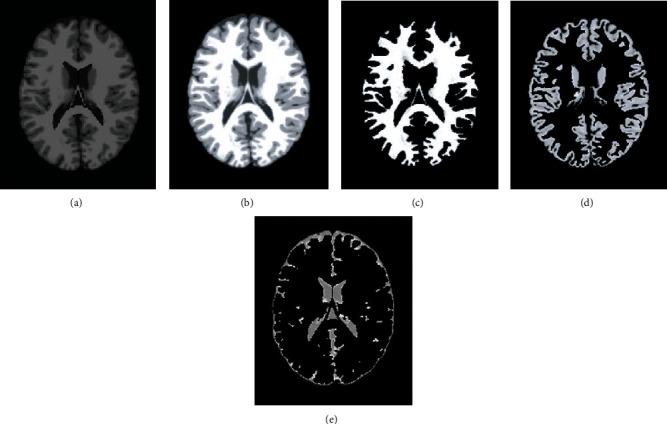

Application of Clustering-Based Analysis in MRI Brain Tissue Segmentation.

The segmentation of brain tissue by MRI not only contributes to the study of the function and anatomical structure of the brain, but it also offers a theoretical foundation for the diagnosis and treatment of brain illnesses. When discussing the anatomy of the brain in a clinical setting, the terms "white matter," "gray matter," and "cerebrospinal fluid" are the ones most frequently used (CSF). However, due to the fact that the human brain is highly complicated in its structure and that there are many different types of brain tissues, the human brain structure of each individual has its own set of distinctive qualities. Because of these several circumstances, the process of segmenting brain tissue will be challenging. In this article, several different clustering algorithms will be discussed, and their performance and effects will be compared to one another. The goal of this comparison is to determine which algorithm is most suited for segmenting MRI brain tissue. Based on the clustering method, the primary emphasis of this research is placed on the segmentation approach that is appropriate for medical brain imaging. The qualitative and quantitative findings of the experiment reveal that the FCM algorithm has more steady performance and better universality, but it is necessary to include the additional auxiliary conditions in order to achieve more ideal outcomes.